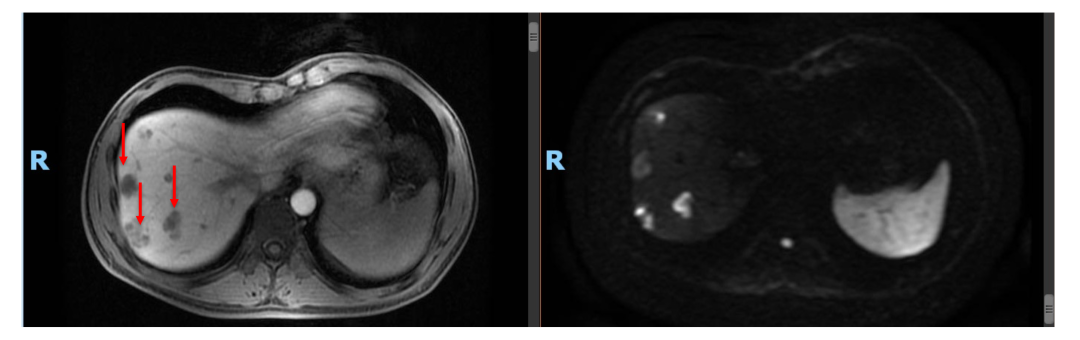

• 2020年11月复查肝内病灶SD(DWI高信号均消失),CEA, CA199正常。ctDNA: 未见明确有害突变。患者予停药(术后免疫治疗共进行约1年)。